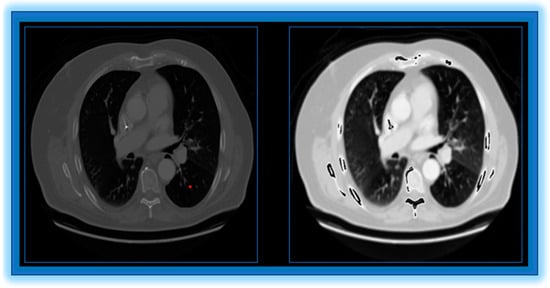

- Convex Hull Lung Region Extraction: In order to concentrate the analysis on the pertinent area, we isolate the lung region.

- Edge Enhancement: Using the unsharp masking filter (UMF) improves the ability to define the image edges.

3.1. Preprocessing